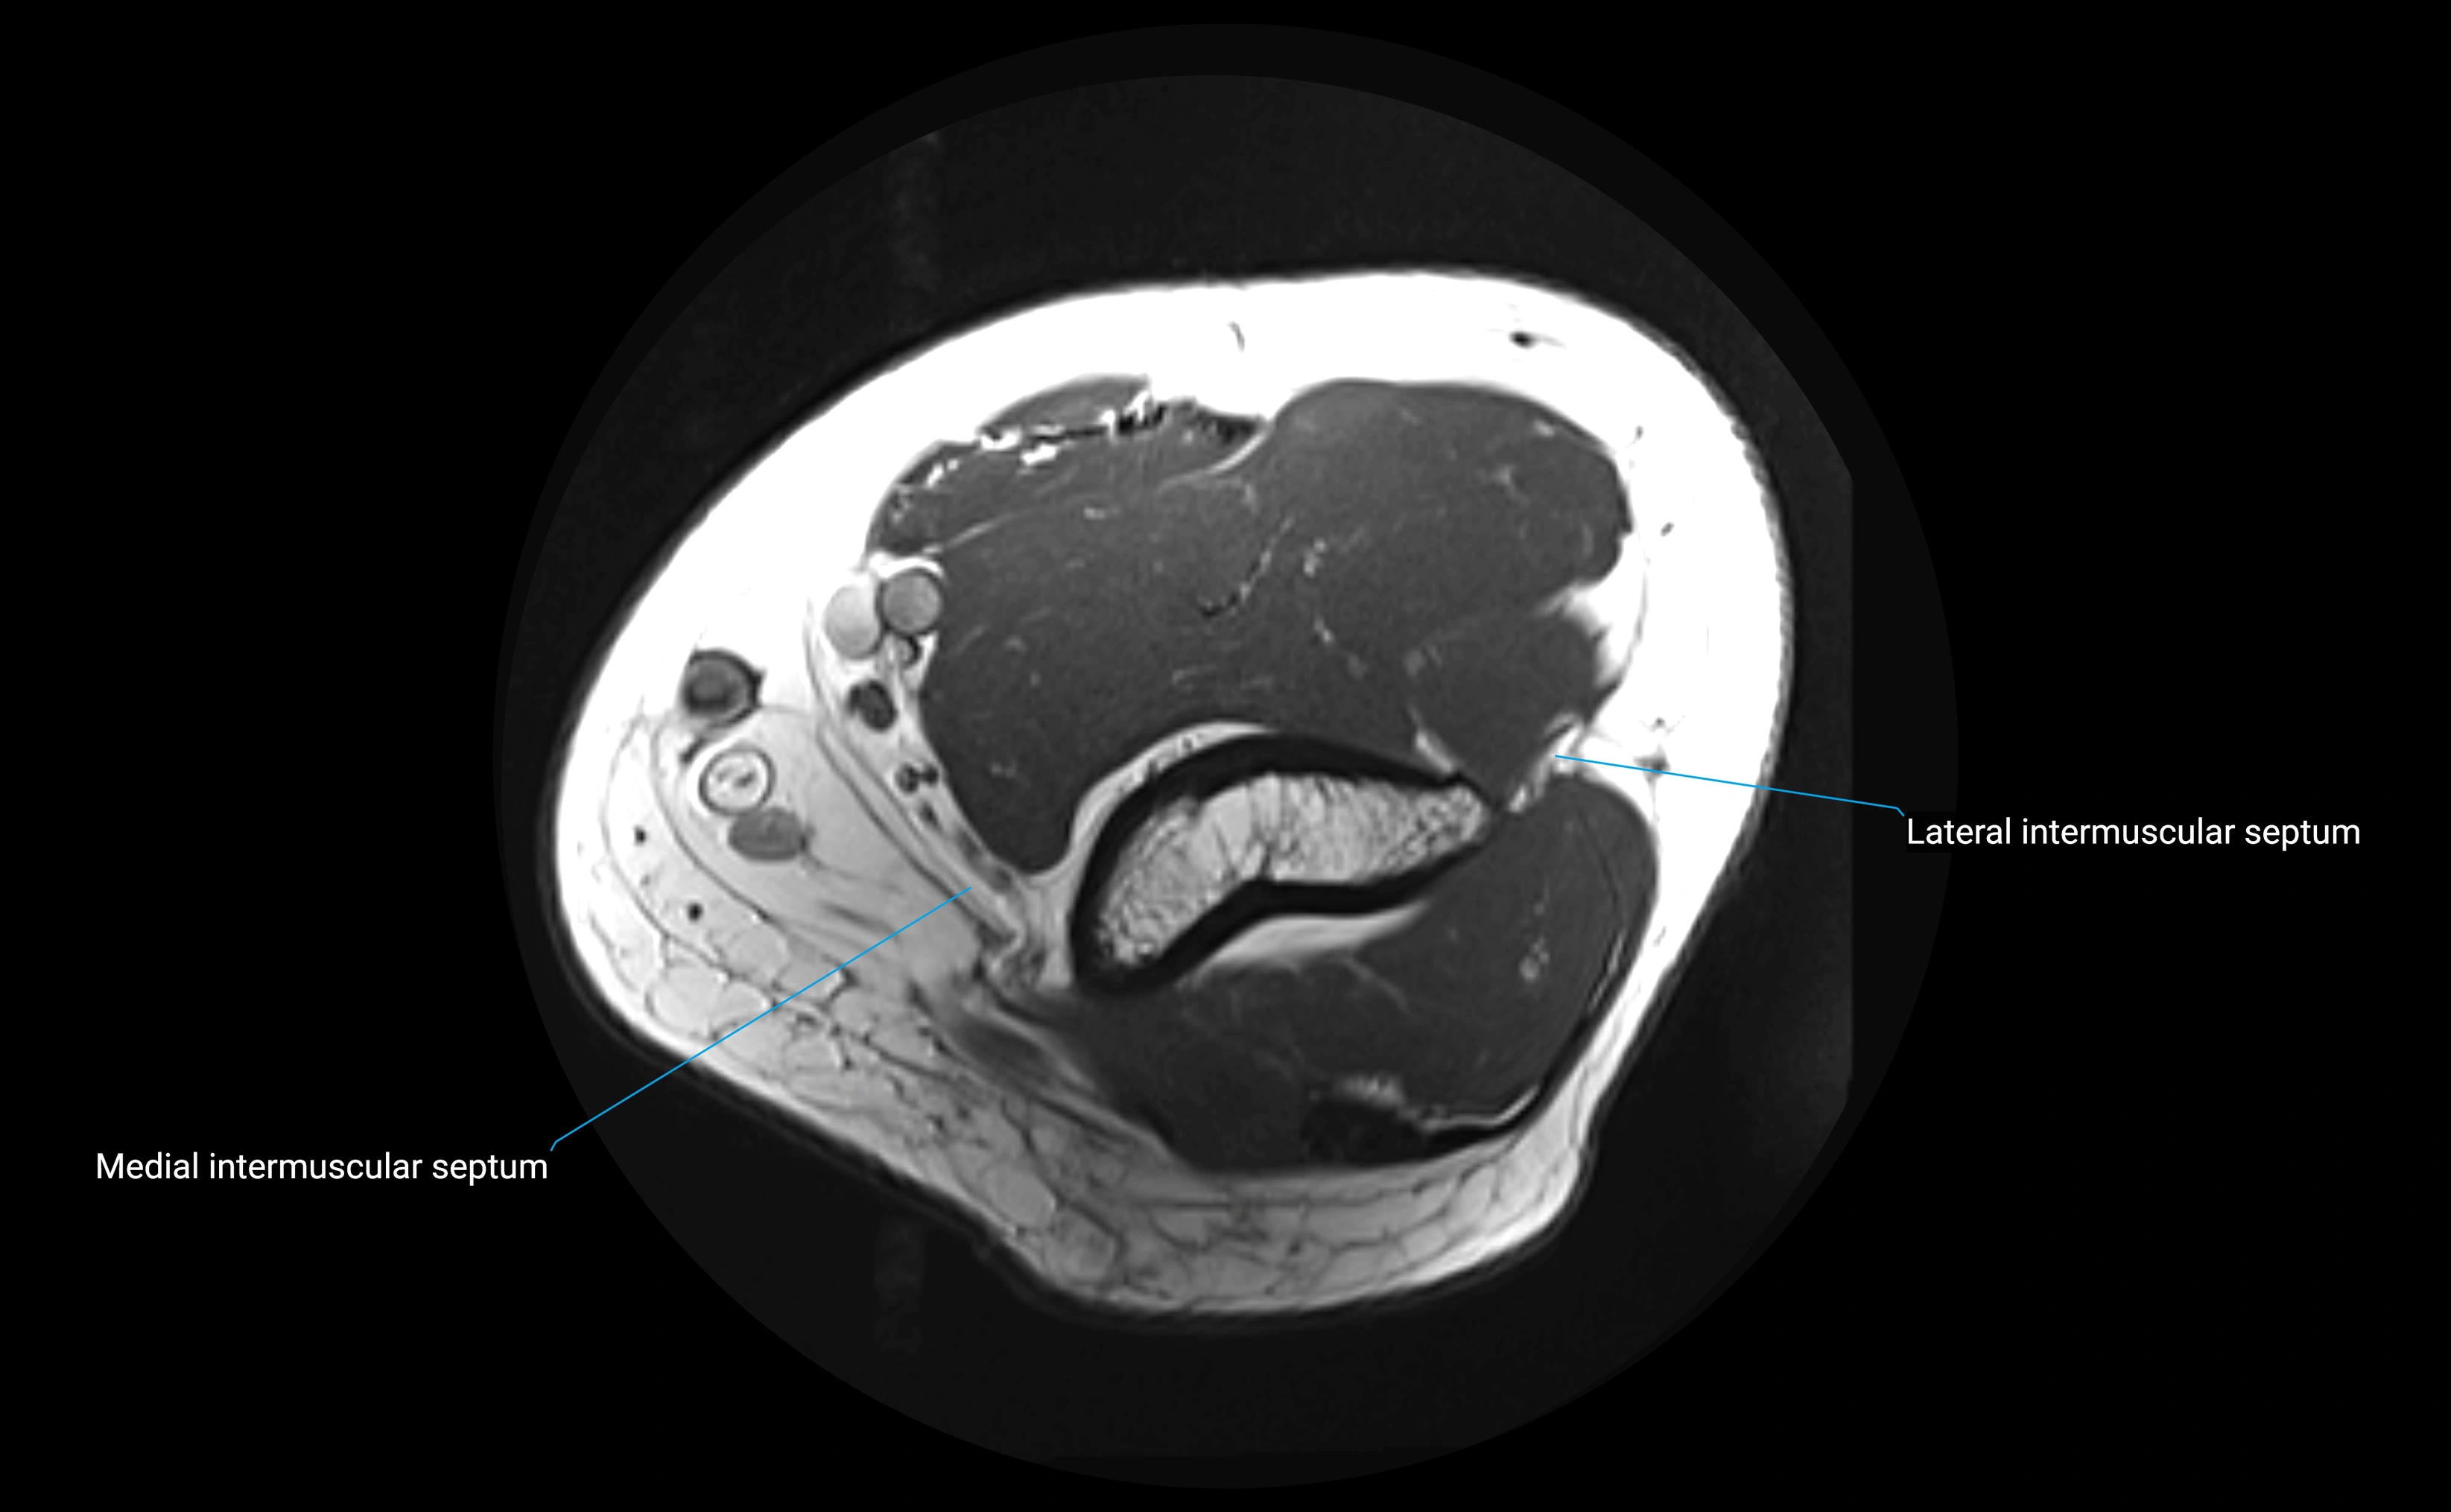

MRI Appearance

T1-weighted images:

• Ligament: low signal intensity (dark), appearing as a continuous band around the radial head.

• Adjacent fat and marrow: bright, creating contrast with the ligament.

• Thickening or disruption indicates injury or fibrosis.

• Joint capsule and synovium seen as thin low-signal lines contiguous with ligament margins.

T2-weighted images:

• Ligament: low signal (dark) with clear delineation from joint fluid.

• Fluid or edema: bright hyperintense, separating or surrounding the ligament in partial tears.

• Complete tear: discontinuity or non-visualization of ligament fibers, often with joint effusion.

STIR:

• Normal ligament: dark band encircling radial head.

• Pathology: bright hyperintense periligamentous signal suggesting edema, sprain, or partial tear.

Proton Density Fat-Saturated (PD FS):

• Normal: dark, well-defined band outlining the radial head.

• Partial tear: irregular or bright hyperintense signal within or adjacent to ligament fibers.

• Joint effusion and reactive synovitis appear bright and are well visualized.

MRI images

image